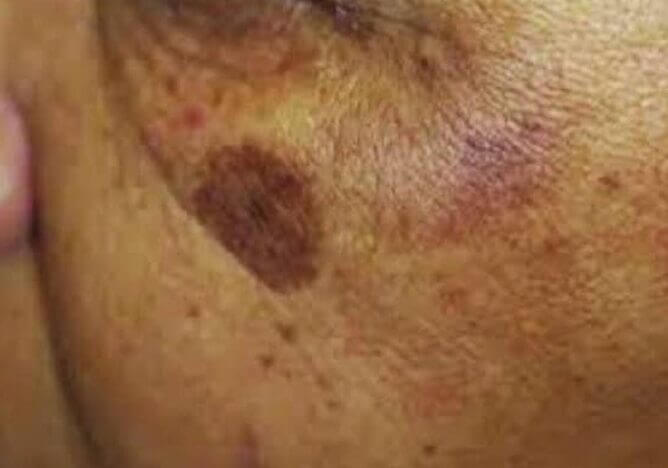

Dyschromia

Gefleckte hyperpigmentierte Läsionen/Flecken

Häufige Hauterkrankung mit unbekannter Pathogenese

Im Zusammenhang mit durch Sonnenlicht und Hormone stimulierten Melanozyten (Erhöhung des Melanozyten-Stimulationshormons, MSH) kommt es zu ungleichmäßigen Zunahmen des Melanins im Gesicht.

Häufiger anzutreffen bei Menschen mit höherer Pigmentierung, kann aber bei allen Hauttypen vorkommen.

So funktioniert es

- Induziert den Keratinozytenumsatz und stellt die normale Pigmentaktivität der Melanozyten in überpigmentierten Bereichen wieder her.

- Dies geschieht an der dermoepidermalen Junktionszone (DEJ).

- Der Bereich zwischen der dermoepidermalen Junktionszone und der flachen Dermis ist die Zieltiefe für die Mikronadelung.

Pigmentierungszustände

Sonnenflecken entstehen durch eine übermäßige Produktion des Pigments Melanin, die durch zu lange UV-Strahlung aus dem Sonnenlicht oder Solarien verursacht wird.

So funktioniert es

- Induziert den Keratinozytenumsatz und stellt die normale Pigmentaktivität der Melanozyten in überpigmentierten Bereichen wieder her.

- Dies geschieht an der dermoepidermalen Junktionszone (DEJ).

- Der Bereich zwischen der dermoepidermalen Junktionszone und der flachen Dermis ist die Zieltiefe für die Mikronadelung.